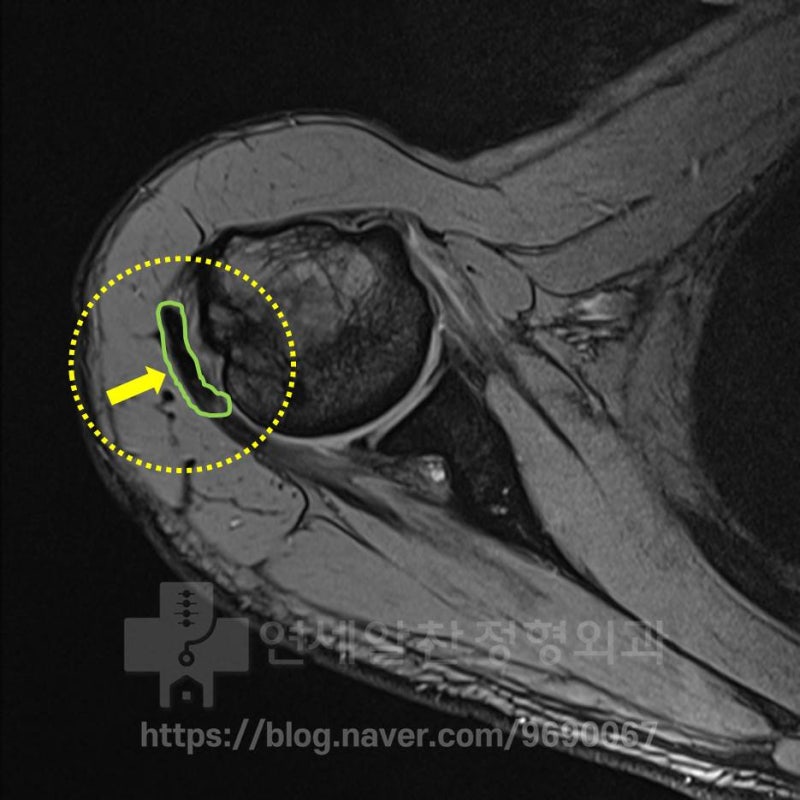

MRI 에서 보면 녹색으로 표시된 부위에 검은 음영으로 표시된 것이 보입니다.

다른 MRI 를 보면 빨간색 점선으로 표시된 부위에서 대결절 부위의 불규칙한 면이 관찰되고 있습니다. 하지만 극상근의 약화는 관찰되나 파열 소견은 관찰되지 않습니다. 환자의 수상 기전과 상기의 검사들은 보았을 때 석회성 건염 보다는 대결절 골절이 발생되었고 그로 인한 불유합이 발생된 것으로 판단됩니다. 첫번째로 가장 안타까운 것은 최초 수상 당시 바로 치료를 제대로 했다면 (이정도의 손상이라면 대결절 골절에 대한 수술적 치료) 지금은 정상적으로 생활하고 운동을 할 수 있었을 것이라 생각됩니다. 그럼 이때 수술한 영상을 확인해 보겠습니다.